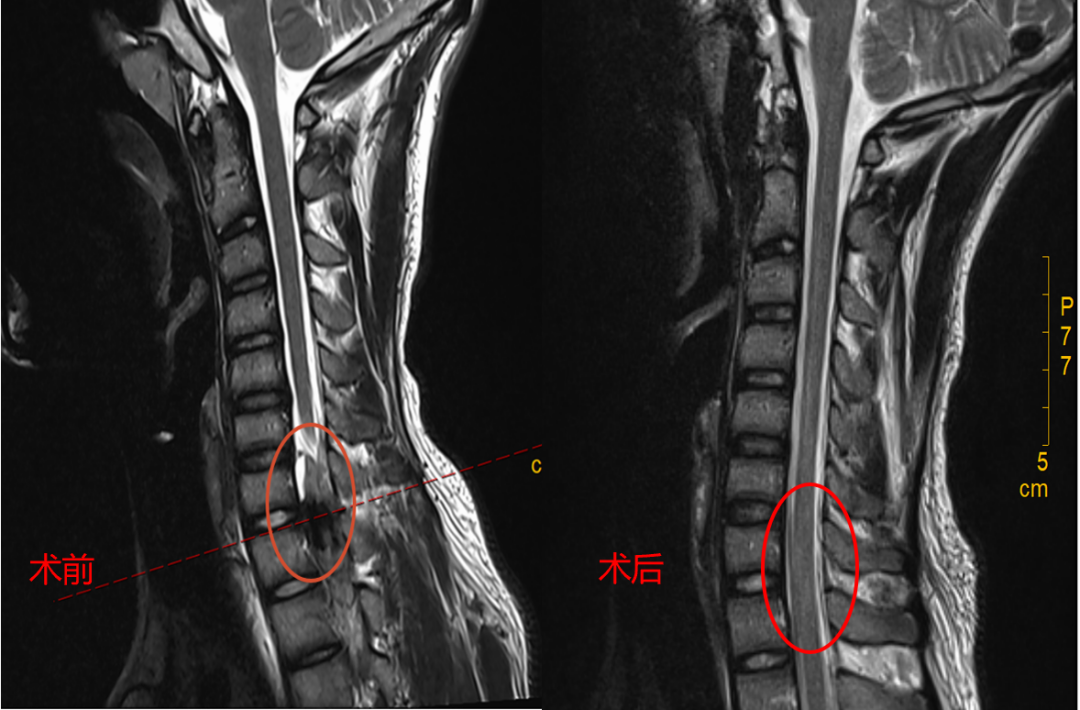

术前、术后磁共振对比:血肿被清除

术中,镜下显示:小吴的椎管内硬膜外存在明显血肿,排除脱出髓核和肿瘤的可能。医疗团队在内镜视野下,小心翼翼地将压迫脊髓神经的血凝块全部清除,整个过程出血量少,创伤小。

术后,麻醉苏醒的小吴惊喜地发现右手又能动了。他激动得说不出话,泪水在眼眶里打转。

在脊柱外科医护团队的优质护理、规范康复训练下,小吴术后两天已基本恢复日常活动。出院后,他已经迫不及待地投入到紧张的学习中去了。